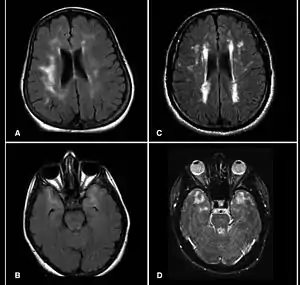

| Brain MRI from patients with CADASIL showing multiple lesions. | |

MRIs show hypointensities on T1-weighted images and hyperintensities on T2-weighted images, usually multiple confluent white matter lesions of various sizes, are characteristic. These lesions are concentrated around the basal ganglia, peri-ventricular white matter, and the pons, and are similar to those seen in Binswanger disease.[2][11] These white matter lesions are also seen in asymptomatic individuals with the mutated gene.[12] While MRI is not used to diagnose CADASIL, it can show the progression of white matter changes even decades before onset of symptoms.